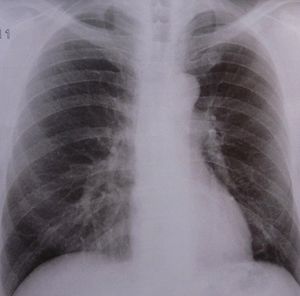

Röntgenbild der Lunge: Mehr Frauen von Krebs betroffen (Foto: pixelio.de/Schütz) |

Bei Frauen nehmen Lungenkrebsfälle zu. Brust- und Prostatakrebs werden wahrscheinlich bei Männern und Frauen die häufigsten Erkrankungen bleiben. Einige Krebsarten treten jedoch sehr rasch häufiger auf. Dazu gehören Tumore der Speiseröhre, die durch einen Säurereflux bei Fettleibigkeit verursacht werden. Zusätzlich nehmen Erkrankungen des Kopfes und des Nackens zu, die durch die Zunahme des humanen Papillomavirus hervorgerufen werden. Die Forscher nehmen an, dass die Zunahme oraler Sexpraktiken dafür verantwortlich ist.